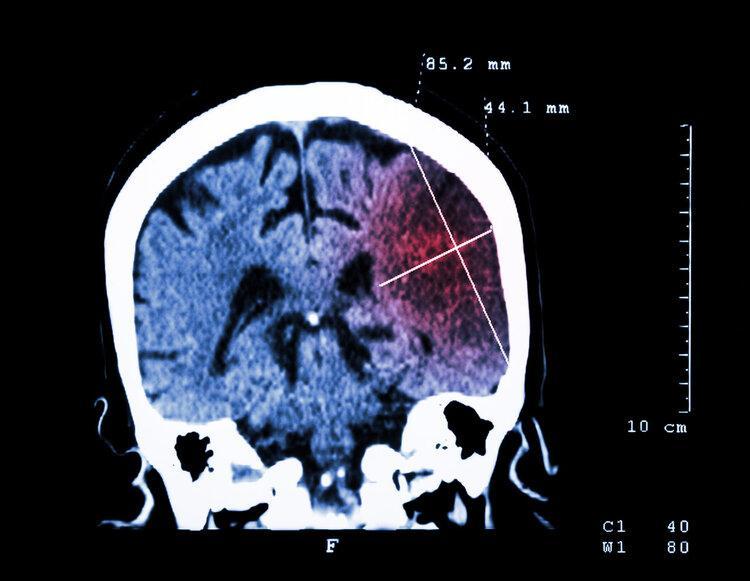

腦梗是指缺血性腦卒中,我們常說的中風大部分就是指腦梗。

腦梗發生後,患者會有口歪眼斜、肢體無力、言語不清等症狀,該症具有極高的致殘、致死率

不少患者在治療後會留下偏癱、失語等後遺症,還可能因此而出現卒中後抑鬱,給後續的生活質量帶來極大影響。